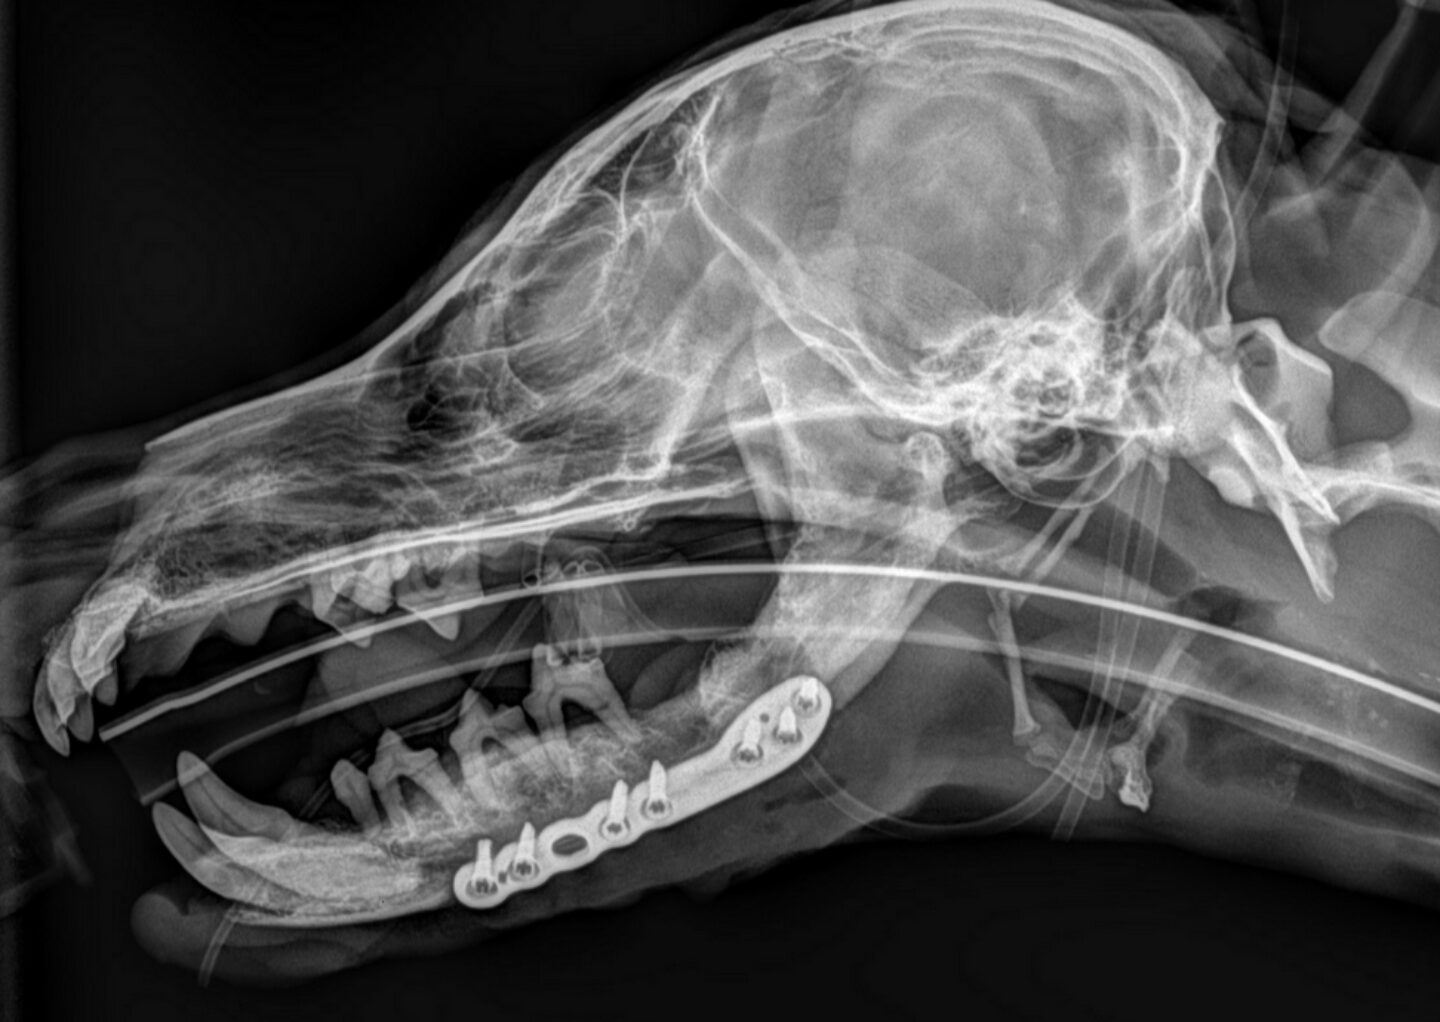

Versorgung von Kieferfrakturen durch Plattenosteosynthese bei parodontalen Kleinhunden

Mini-Plates bei Mini-Hunden

Kieferfrakturen können bei parodontalen Kleinhunden spontan oder durch leichtes Trauma, auch iatrogen in Zahnsanierungen, auftreten. Es gibt verschiedene Optionen zur Versorgung von Mandibulafrakturen in der Tiermedizin. Besonders bei sehr kleinen Hunden mit fortgeschrittener Parodontitis kann die Versorgung eine Herausforderung darstellen. Dr. Anna Draschka, EMSAVM Dentistry, Fachtierärztin für Kleintierzahnmedizin vom Tierzahnzentrum in München und Dr. Constantin Post, Diplomate ECVS, Fachtierarzt für Chirurgie v